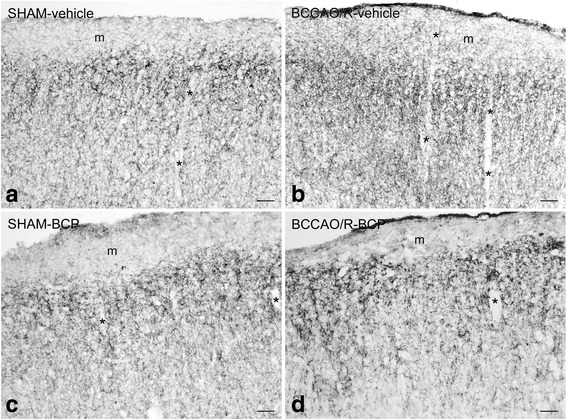

The antibodies against CB1 and COX-2 were the only ones to produce a reliable immunostaining in tissue sections of rat cerebral cortex. For this reason, the following immunohistochemical data are based exclusively on the immunoreactivity obtained with them.

Immunohistochemistry

In order to associate the molecular changes observed by HPLC and western blot analyses and the tissue morphology, immunoreactivities to CB1 and COX-2 were also examined in the cerebral cortex (Figs. 4, 5). All markers labeled neuronal structures distributed throughout the rostro-caudal extension of the frontal cortex (Figs. 4, 5) and the temporal-occipital cortex (data not shown).

The CB1 receptor-antibody labelled a dense to moderate plexus of beaded fibers and some neuronal cell bodies distributed throughout the cortical layers in both vehicle- and BCP-treated rats (Fig. 4). As a general rule the density of labelled nerve terminals and fibers appeared higher in BCCAO/R animals (Fig. 4b, d) than in the sham-operated ones (Fig. 4a, c).